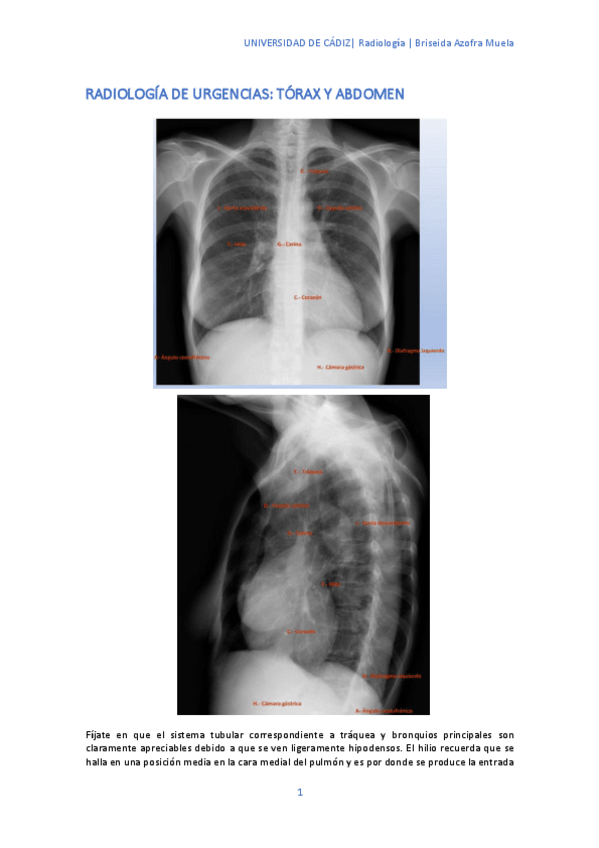

He publicado nuevos apuntes de 3º Radiología y Medicina Física. Protección Radiológica: Radiologia-de-urgencias-torax-y-abdomen.pdf

15 páginas